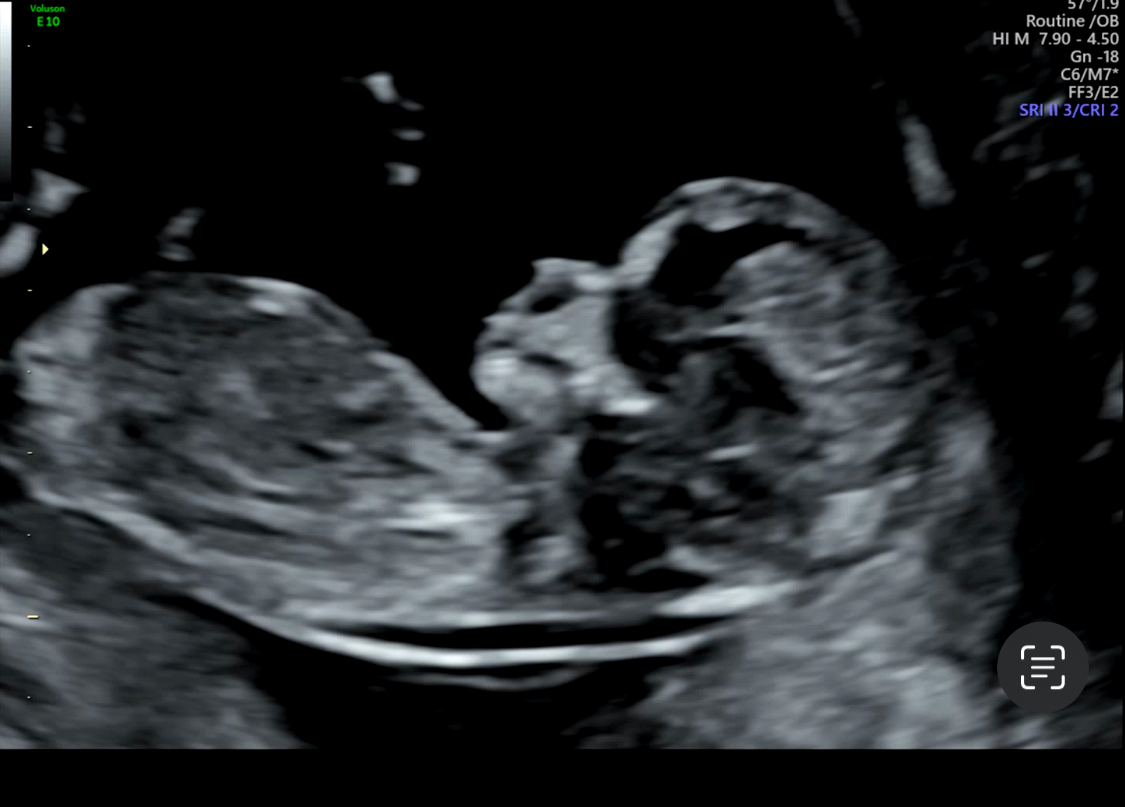

그리고 마지막으로 봐준 입체초음파

헐... 입체초음파는 그냥 초음파랑 느낌이 너무 다른데요

ㅋㅋㅋㅋㅋㅋㅋㅋㅋ 머리가 어금니같아.. 푸하하핫

좀 더 야무지게 크면 이뻐지겠지?

다리가 너무 짧은거 아니냐고 걱정했드니

다 이래요 엄마~하고 다리도 이뿌게 꼬고있어요! 하심